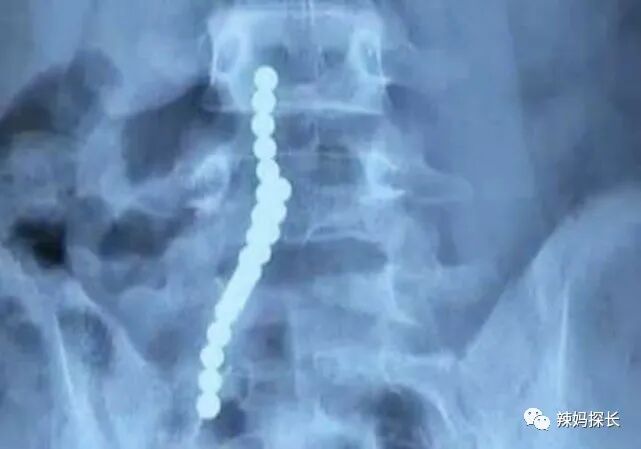

如果说自家孩子比较喜欢玩小磁铁的话,那家长一定要当心了,可千万不能够让孩子单独的长时间的玩,因为小磁铁是很容易会被误食的。磁力球的体积比较小,如果是说孩子吞下了小磁铁,尤其是一次性吞下了两块以上的话,那孩子的肠道就有可能会因此受到影响。